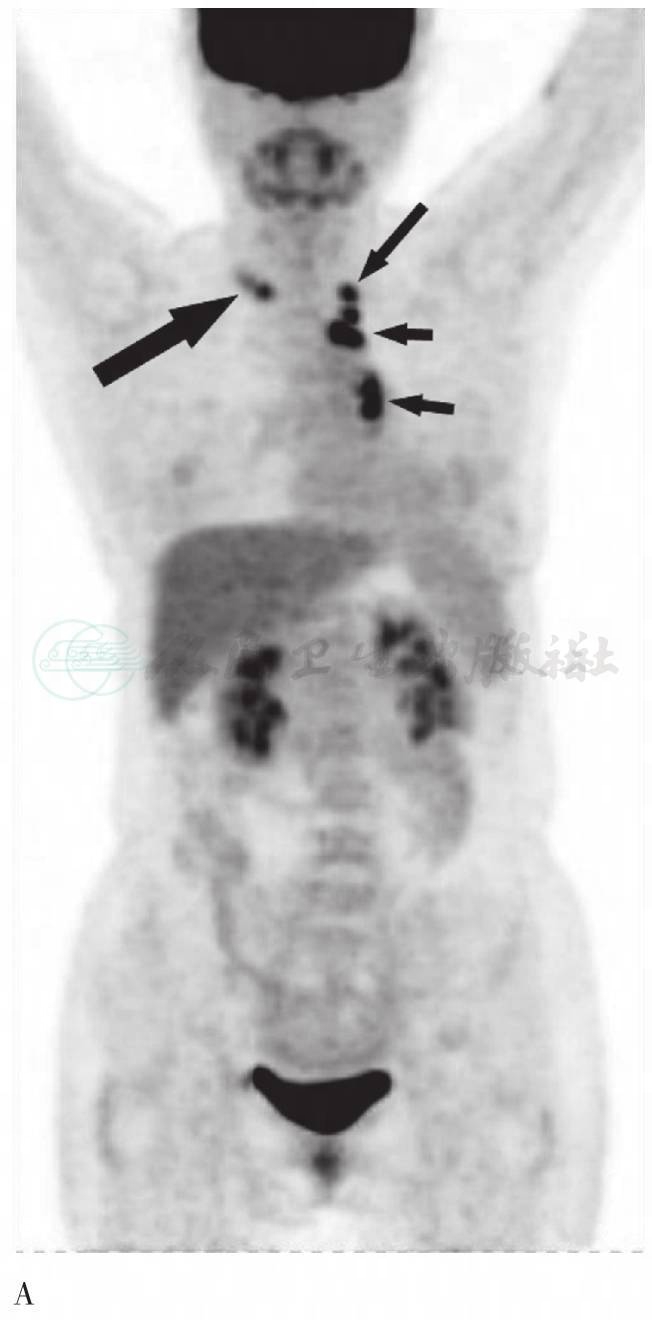

图2 2009年6月3日FDG PET/CT图像

A. PET MIP显像,颈部横断层图;B. CT纵隔窗;C. PET图像;D. PET/CT融合图像,胸部横断层图;E. CT纵隔窗;F. PET图像;G. PET/CT融合图像。右锁骨上多个淋巴结,边缘可见多发钙化,放射性摄取增高,SUVmax为4.1,延迟显像为5.2(长粗箭头);左锁骨上淋巴结放射性摄取增高,SUVmax为5.0,延迟显像为6.7(长细箭头)。CT示右上肺条索影伴多发钙化灶,双肺门及纵隔内多发钙化灶。左上纵隔可见3个淋巴结影放射性摄取异常增高,SUVmax为5.1、9.4,延迟显像为8.1、12.3;左肺术后改变,左肺门与降主动脉动脉间软组织影放射性摄取异常增高,SUVmax为7.5,延迟显像为10.7(短细箭头)